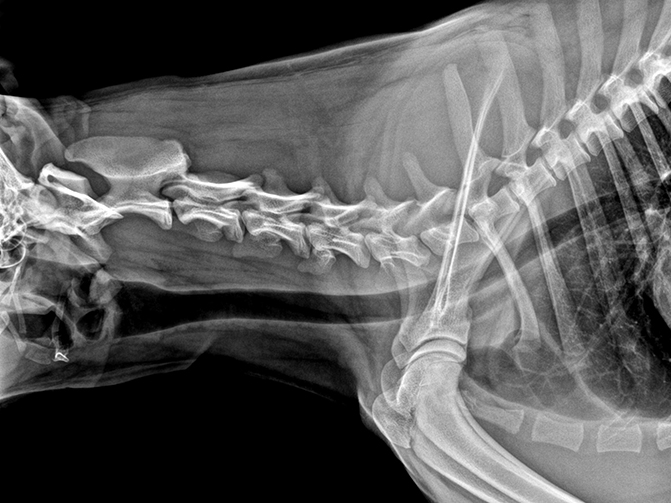

VET-528